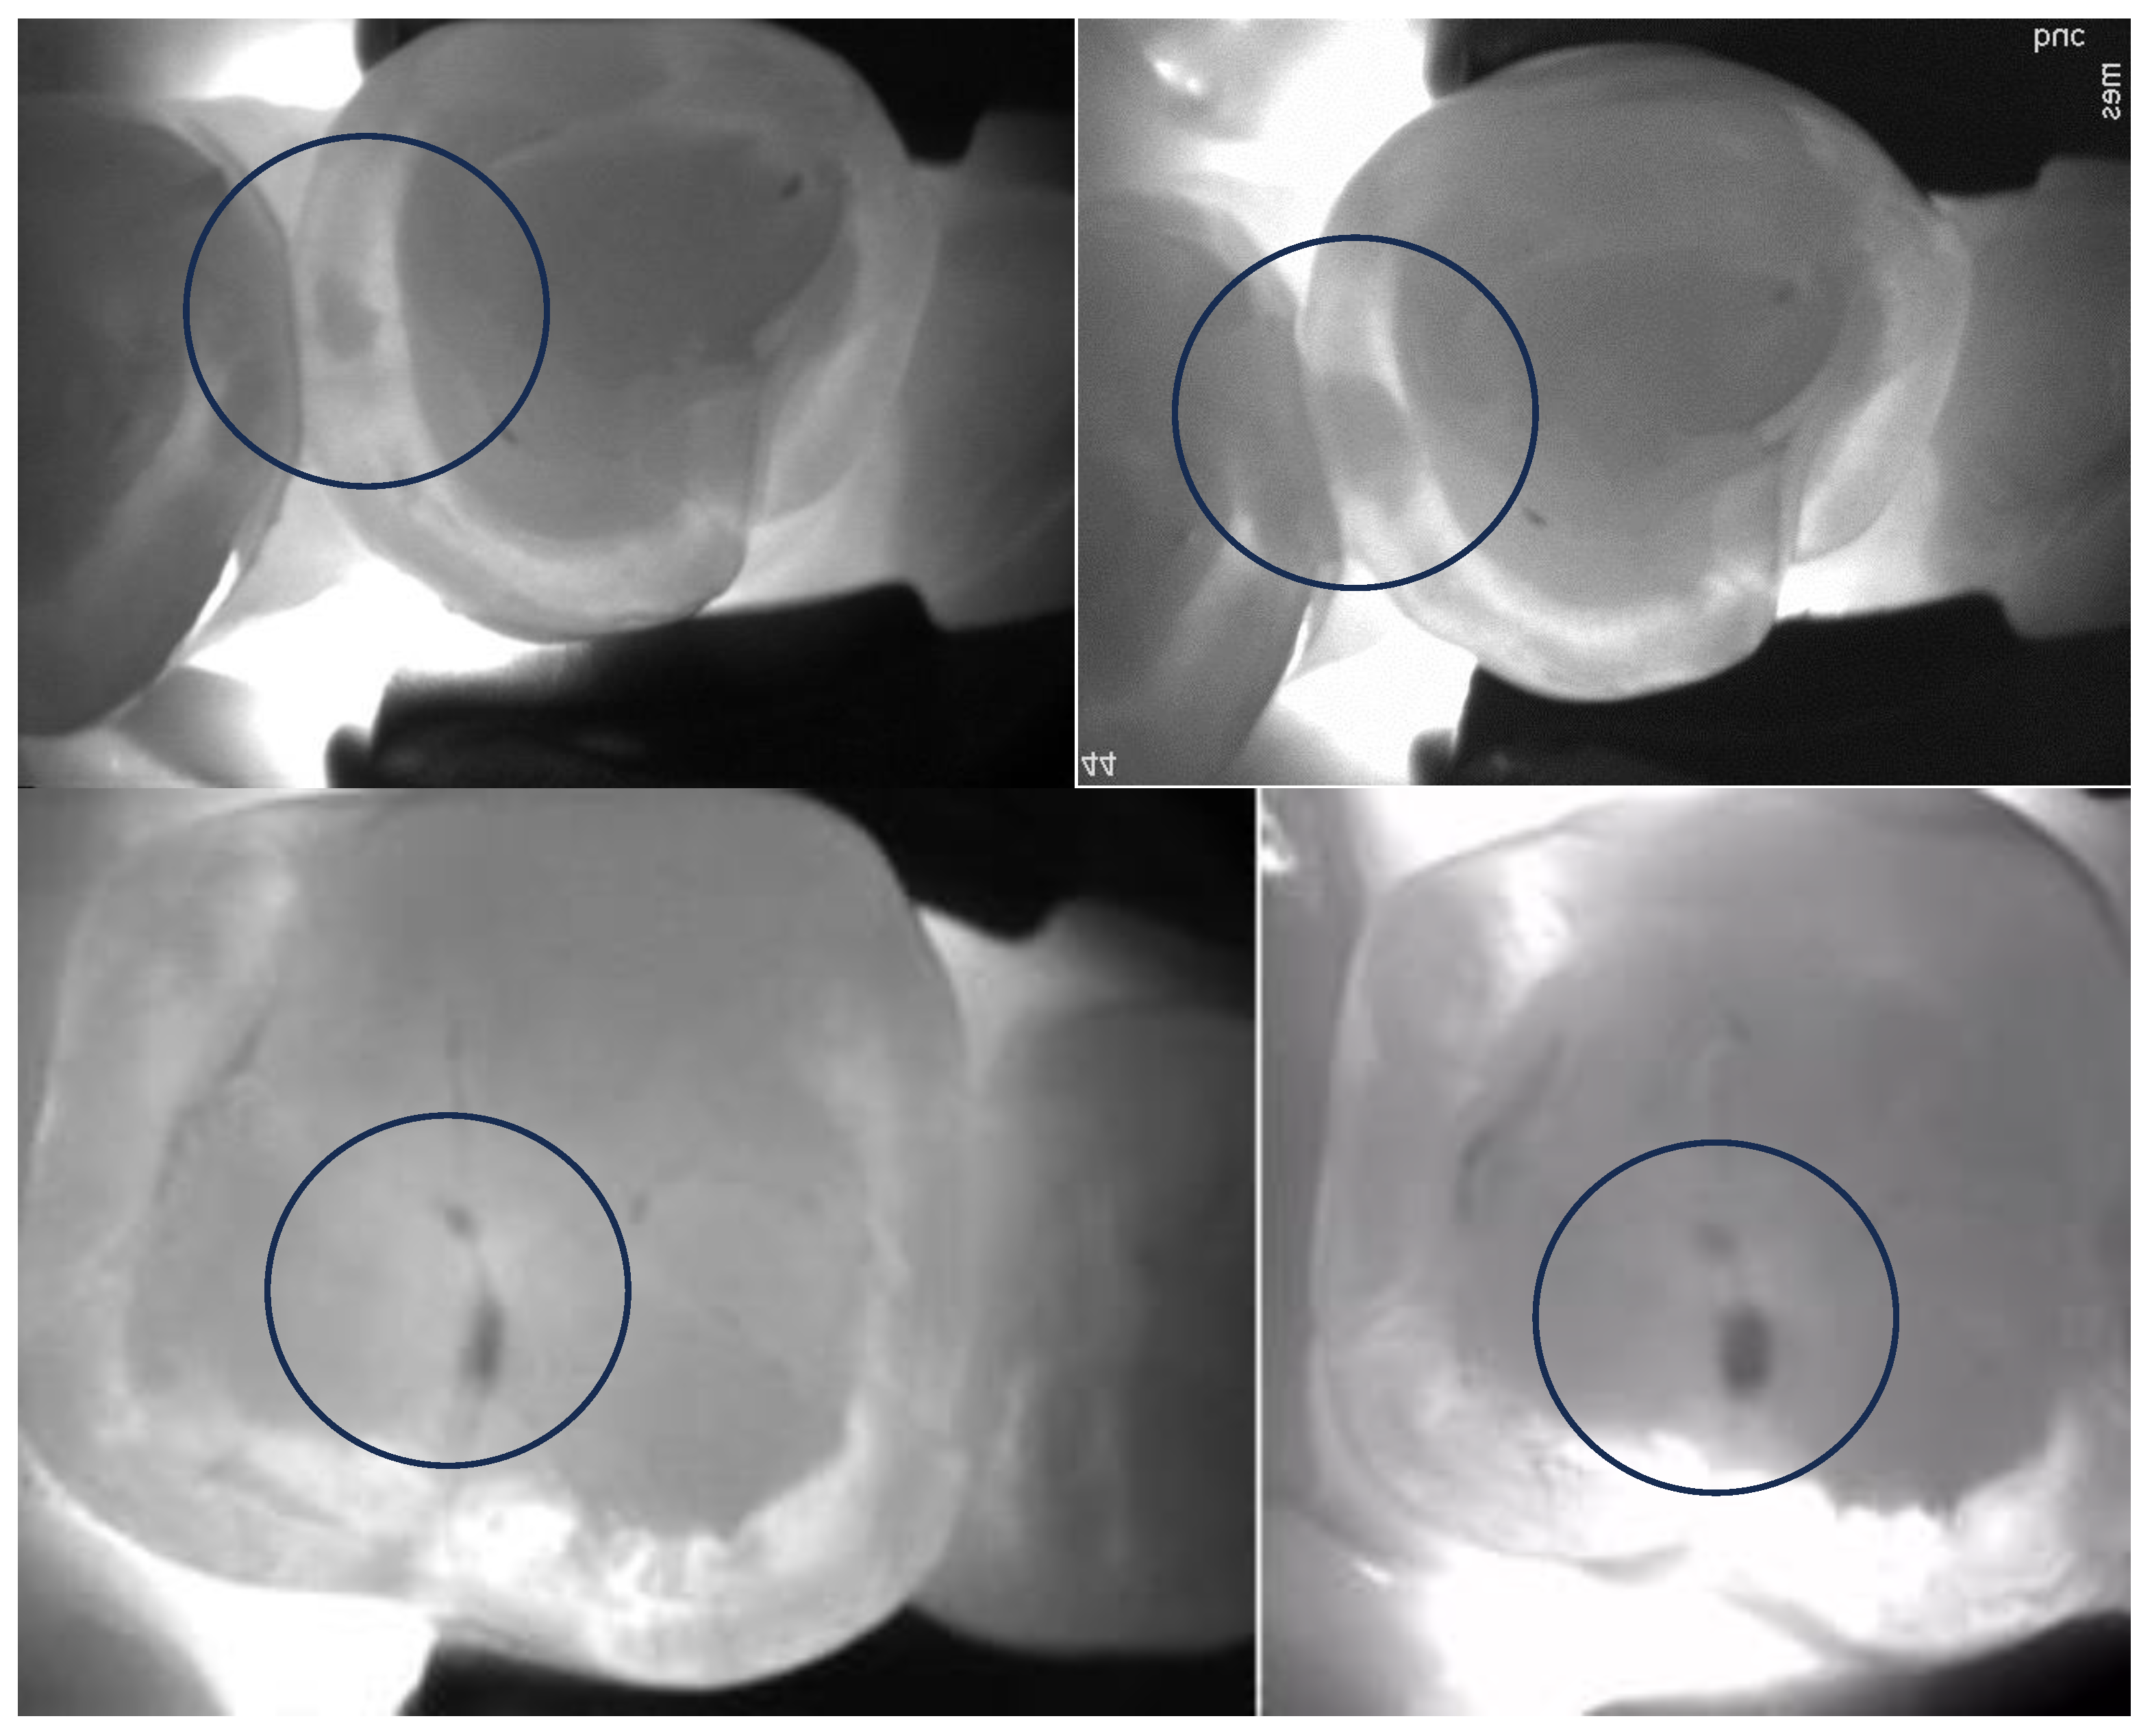

4.1.2. The Use of Near-Infrared Transillumination in Caries Detection and Monitoring

- Mohamed Nur, M.; Vazquez, L.; Anton, Y.O.C.; Giacobino, C.; Krejci, I.; Abdelaziz, M. Near-Infrared Transillumination for Occlusal Carious Lesion Detection: A Retrospective Reliability Study. Diagnostics 2022, 13, 36. [Google Scholar] [CrossRef]

- Abdelaziz, M.; Krejci, I. DIAGNOcam—A Near Infrared Digital Imaging Transillumination (NIDIT) technology. Int. J. Esthet. Dent. 2015, 10, 158–165. [Google Scholar] [PubMed]

- Litzenburger, F.; Lederer, A.; Kollmuß, M.; Hickel, R.; Kunzelmann, K.-H.; Heck, K. Near-infrared transillumination with high dynamic range imaging for occlusal caries detection in vitro. Lasers Med. Sci. 2020, 35, 2049–2058. [Google Scholar] [CrossRef] [PubMed]